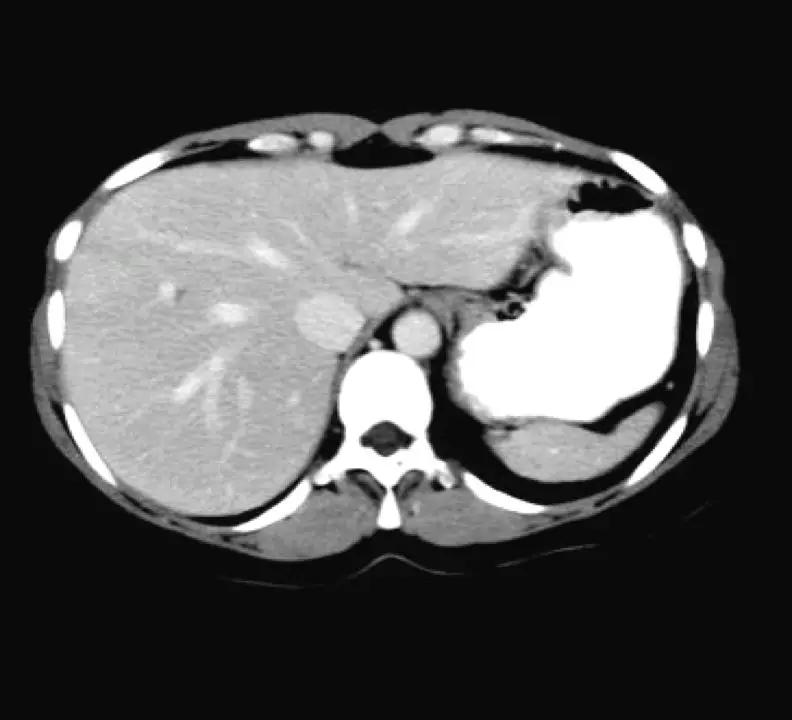

密度分辨率

密度分辨率是指在低对比度的情况下分辨物体密度差别的能力,常以百分数表示。

在CT图像中,物体的密度经过量化处理(即AD转换)后转化为CT值,并直接作为图像灰度值。一般来说,对于相同的图像,量化精度越高,密度分辨率就越好。 由此密度分辨率还与物体的大小、与背景的对比度、噪声水平有关。